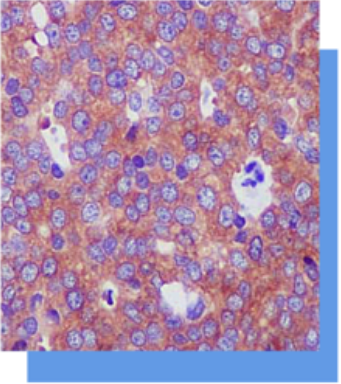

Laminin是细胞外基底膜的主要组成成分,分布

于基底膜和细胞外基质、神经鞘细胞以及平滑肌

细胞。表达于乳腺的肌上皮细胞,在鉴别乳腺化

生性癌中有一定意义。 有助于研究在肿瘤浸润和

转移时基底膜的变化。